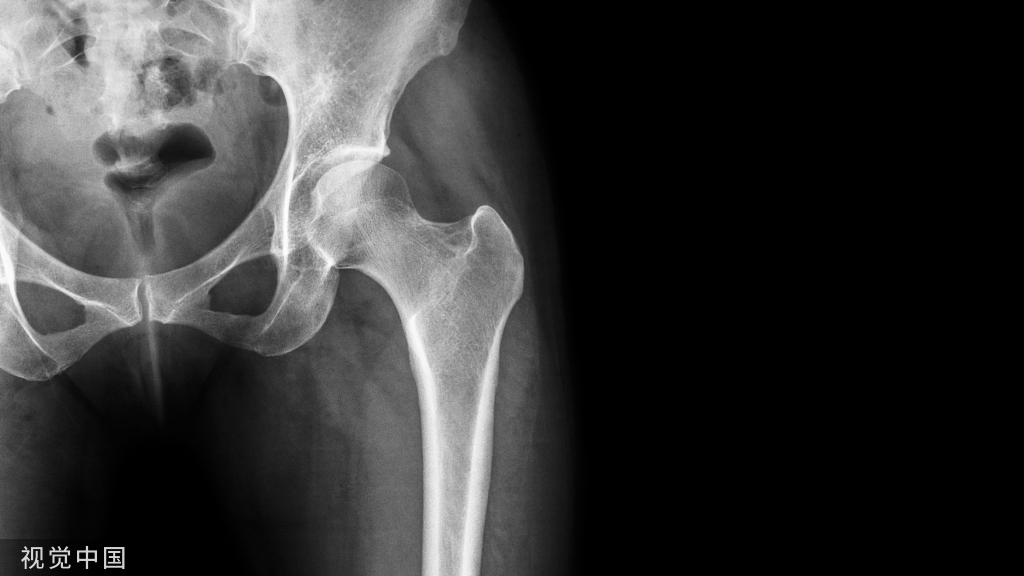

Markus Weber测量了18具身体标本在骨盆正位X线片和CT上的腿长(LL)、整体长度(GO)和股骨偏移量(FO)的变化。四名检查员进行了两次X线片测量。X线和CT测量之间的平均差异为:LL为1.0  mm, GO为0.6mm, FO为1.4mm。1%的放射学LL, 15%的GO和35%的FO测量超出了5毫米的公差极限。x线片用于测量LL/GO变化似乎是可以接受的,但不能反映THA的FO变化。

通过比较术前(A)和术后(B)骨盆的放大校正X线片,评估LL(#)、GO(+)和FO(*)的变化.